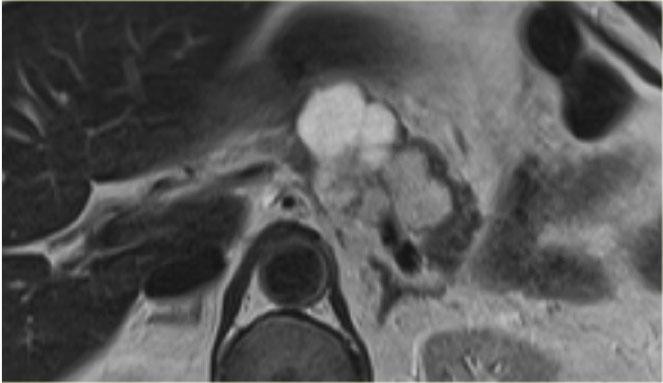

Đây là một ví dụ điển hình khác về u nang tuyến thanh dịch (hình).

Có tổn thương vi nang với sẹo trung tâm ở đầu tụy.

Bệnh nhân tự sờ thấy khối ở bụng.

Ngoài ra không có triệu chứng nào khác.

Do phẫu thuật cắt bỏ đòi hỏi can thiệp ngoại khoa lớn, quyết định được đưa ra là theo dõi tổn thương.

Trong 5 năm theo dõi, tổn thương không tăng kích thước và bệnh nhân không có triệu chứng gì thêm.